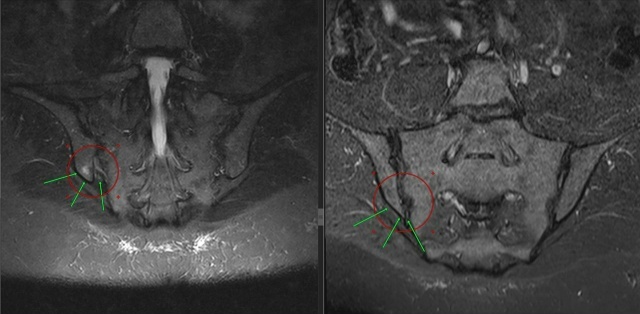

Результаты подтвердили: сакроилеит.

На снимках видна яркая белая зона в области костной ткани - это активное воспаление в правом крестцово-подвздошном суставе.

(Прикладываю МРТ — видите эту белую область справа? Это и есть очаг проблемы)

Вот она, причина года мучений. Причина, которую упустили все предыдущие специалисты.